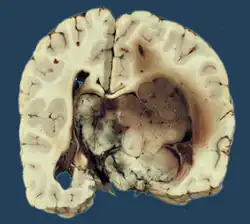

Plexuspapillom. Ausgedehnter Tumor im Bereich des rechten Seitenventrikels mit Mittellinienverlagerung.

Das Plexus-choroideus-Papillom, kurz Plexuspapillom, ist ein seltener gutartiger Hirntumor, der von der Deckschicht (Epithel) des Adergeflechts (Plexus choroideus) ausgeht. Plexuspapillome sind seltene Tumoren, die nur etwa 0,5 % aller Hirntumoren ausmachen. Ganz überwiegend sind Kinder und Jugendliche betroffen.[1] Das Plexuspapillom führt zu einer Erhöhung des Hirndrucks mit Kopfschmerz, Übelkeit und Erbrechen. Die Diagnose wird durch eine Magnetresonanztomographie gestellt. Nach operativer Entfernung ist die Heilungsaussicht sehr günstig, weswegen der Tumor nach der WHO-Klassifikation der Tumoren des zentralen Nervensystems als Grad 1 eingestuft wird.